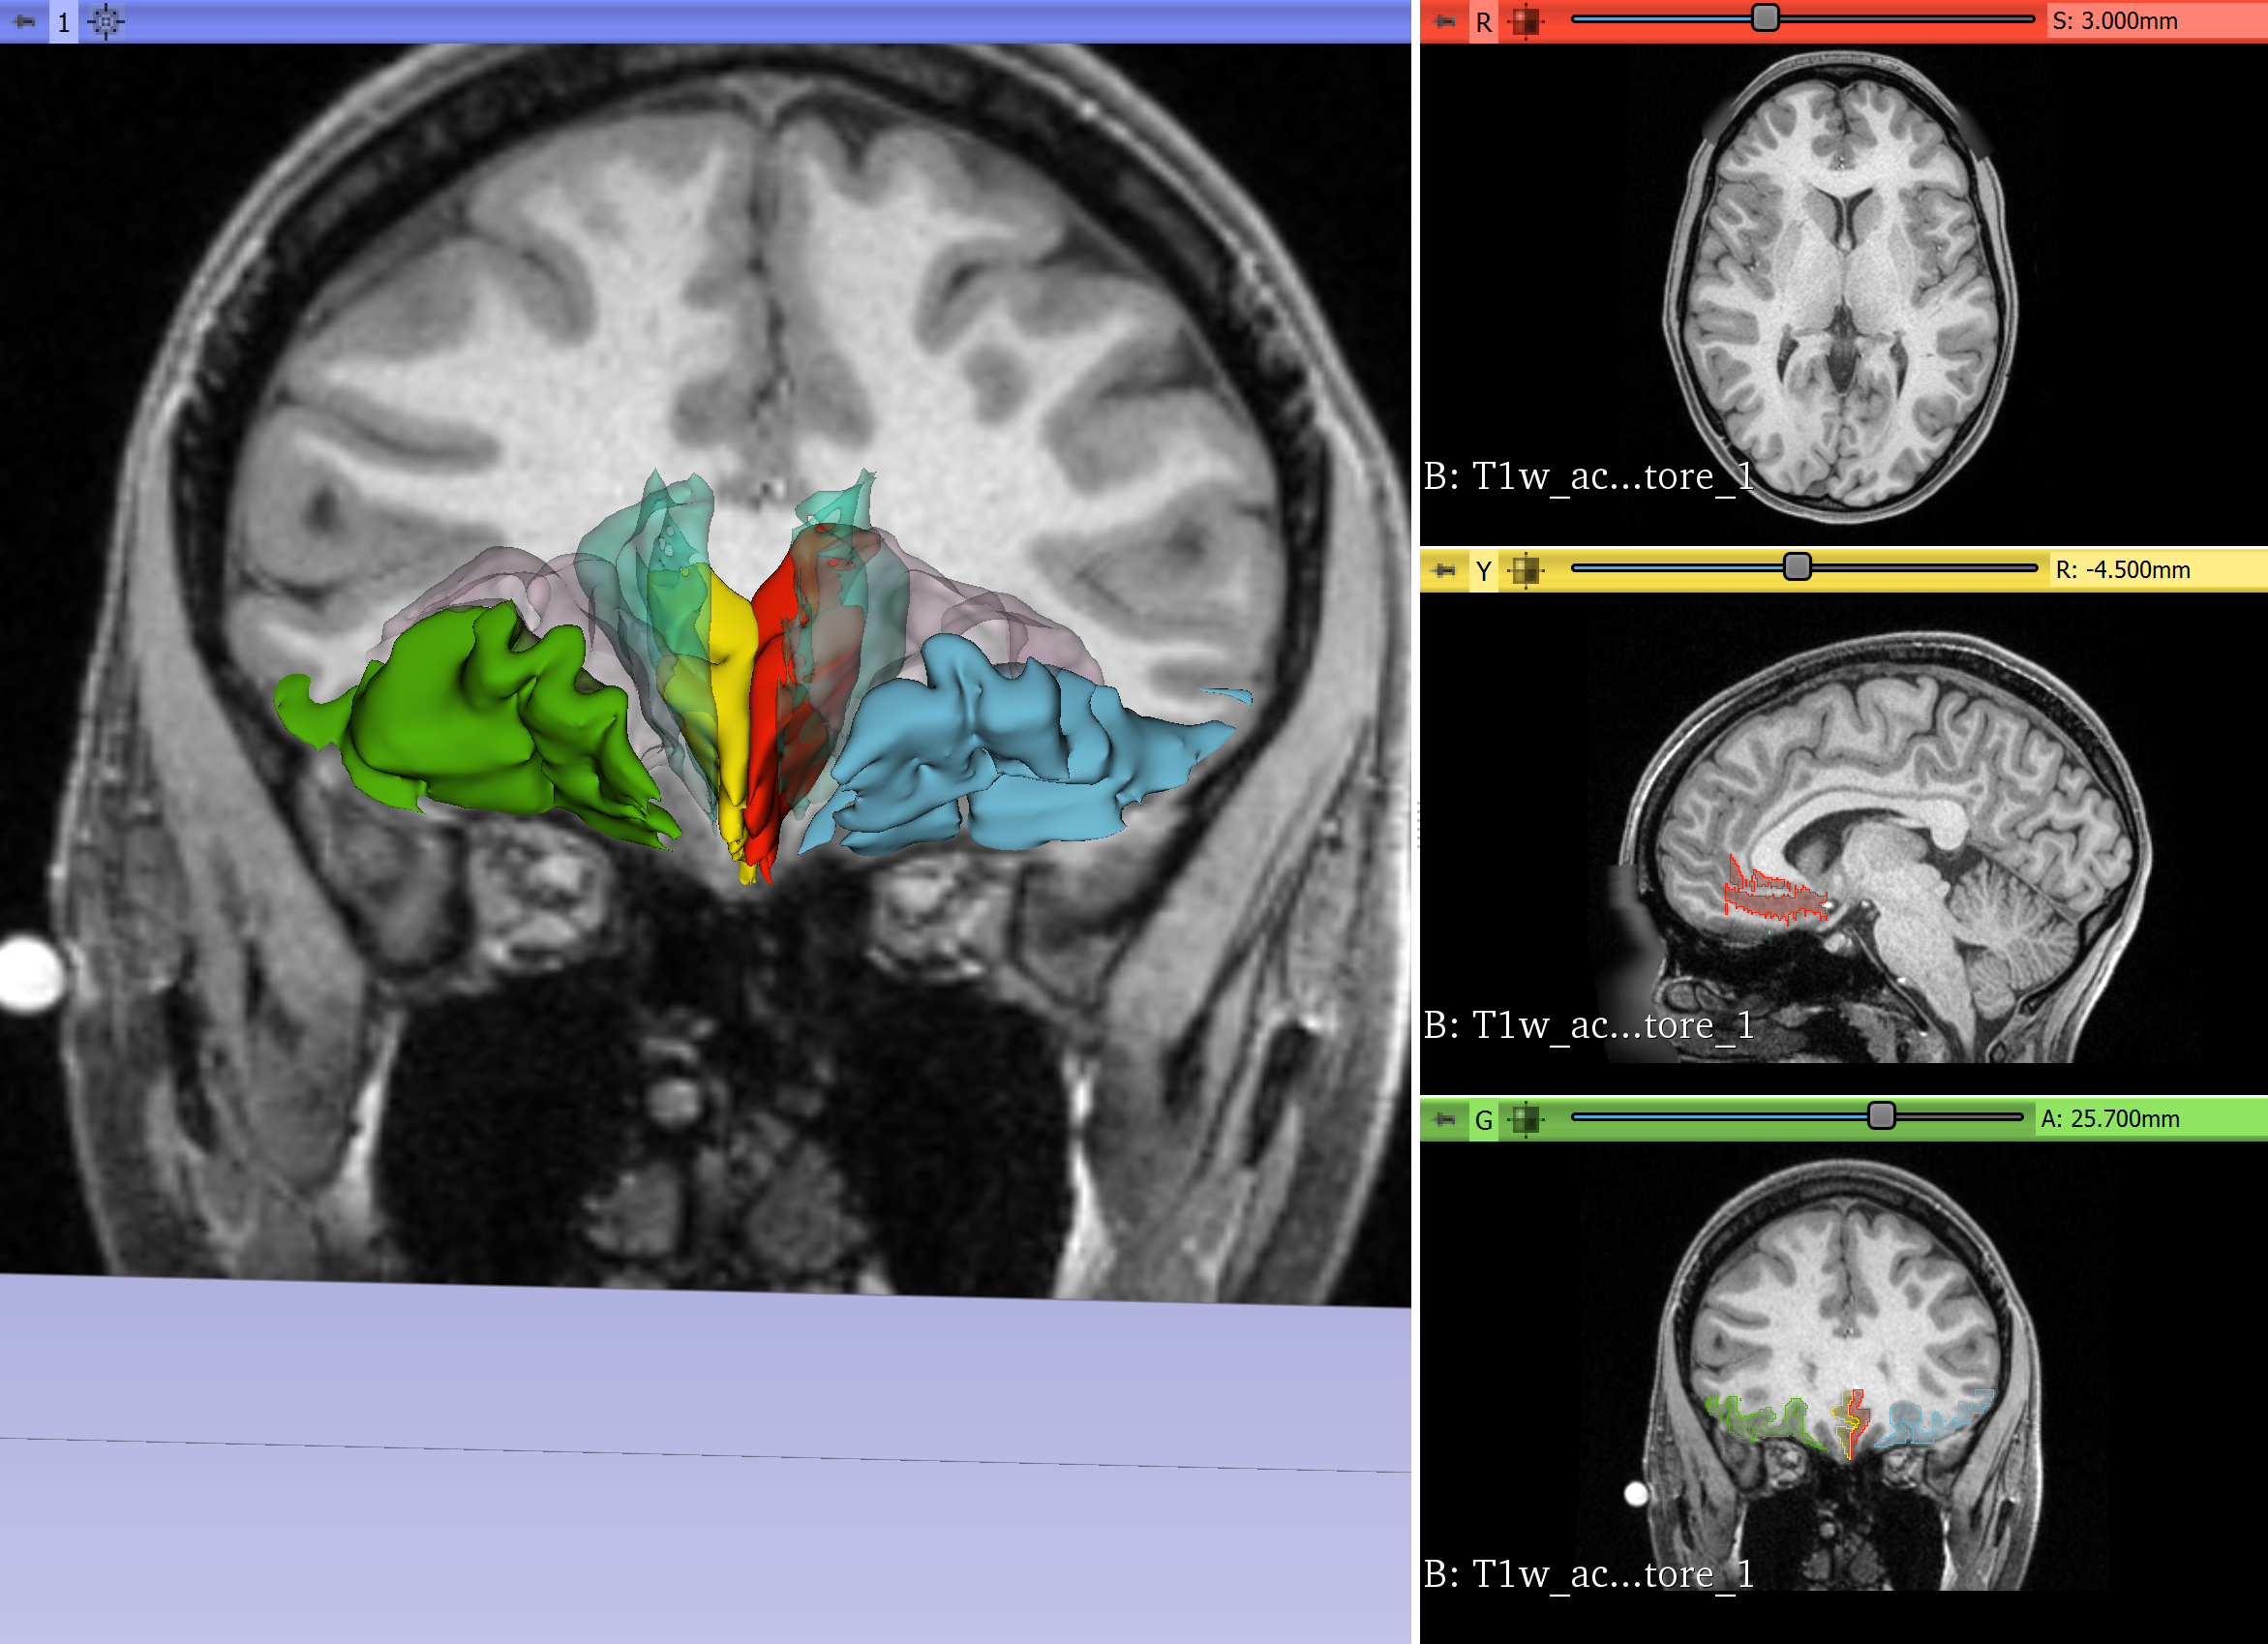

The orbitofrontal-subgenual circuitry is important for the treatment of major depressive disorder (MDD) using non-invasive treatments in psychiatry, such as transcranial magnetic stimulation (TMS) or invasive neurosurgical approaches such as Deep Brain Stimulation (DBS). The anatomical structures involved in this circuitry are the orbitofrontal cortex, Brodmann’s area 11(BA 11), the Subcallosal area, BA 25 and the fiber tract that interconnects these two cortical areas, namely the frontopolar bundle. The two cortical areas of this circuitry can be targets for TMS procedures or DBS interventions.

- We will segment the orbitofrontal cortex and the subcallosal area using SLICER in the individual subject brain using T1 MRI data.

- We will connect these two cortical regions using the tractographic white matter query language (WMQL) software on diffusion MRI data of the same subject.

- Segmentation of orbitofrontal cortex and subcallosal area successfully performed on T1 data.

- Whole brain DMRI tractography successfully performed.

- Diffusion and Structural data registered.

- WMQL query performed.